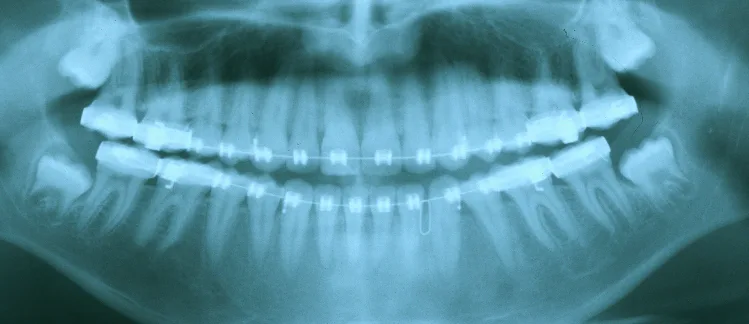

Impacted Teeth

Baby teeth erupt into the mouth in a specific sequence. They then are replaced by adult teeth over the years. The specific eruption pattern helps the jaw bones to grow and develop to their standard size. However, sometimes a baby’s tooth becomes so severely decayed that your dentist removes it. When that happens, the growth of the jaw is compromised. As is often the case, the neighboring teeth start collapsing into the newly vacated space. The dental collapse leads to a physical blockage to the eruption path of the adult teeth. Consequently, the adult tooth then becomes trapped or impacted. But this is not the only way teeth get impacted.

At times, the jaw doesn’t grow enough to accommodate all of the adult teeth. Wisdom teeth are the last set of teeth that come into the mouth. As such, there may not be enough room left for them to come in straight. It is not uncommon to see the wisdom teeth tipping forward and jamming up against the front tooth. These teeth often cause pain and discomfort to the patient and need to be removed.